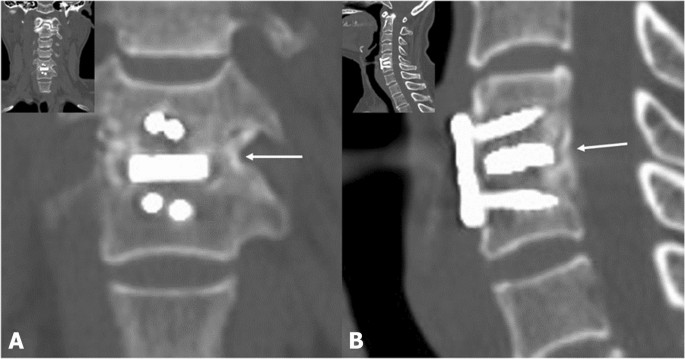

Dynamic lateral radiographs were used to assess ISM in a 150% magnified view between the most prominent point of the spinous process in the fusion segment. More than 1 mm change of ISM between 6 weeks and 12 months simultaneously post-operatively was regarded as pseudoarthrosis22. In the lateral radiograph, cage subsidence was defined as > 3 mm loss at the one-level segment heights, which were calculated as the mean anterior and posterior vertebral body heights between the upper and lower margins of the upper and lower vertebral bodies, respectively, at the fused segment between immediate post-operative and post-operative 12 months (Fig. 2)23. A CT scan was used to evaluate the fusion status, which is defined as bone bridging formation around graft material in the fusion segment 12 months post-operatively (Fig. 3). Fusion status was assessed based on the agreement of two orthopedic surgeons with 5 and 8 years of experience who were not involved in the treatment. Inter- and intra-observer agreements were assessed using Cohen’s kappa value (95% confidence interval) according to Landis et al.’s method24. Two reviewers analyzed the CT scans and dynamic radiographs for bone bridging formation around the cage and ISM after a 3-week interval to investigate the intra-rater agreement. Disagreements in the radiographic results for assessment of fusion status were resolved through discussion between reviewers with a unanimous decision. All radiographic parameters were measured using an internal caliper tool in the software (Centricity 3.0, General Electric Medical System, Milwaukee, WI, USA).

Inter-spinous motion (ISM) between fusion segments 12 months post-operatively in the PEEK and BGC groups was 0.54 ± 0.37 and 0.54 ± 0.37 mm, respectively (P = 0.562). No subsidence occurred at 12 months post-operatively in the two groups. However, one case in each group showed pseudoarthrosis in the dynamic radiograph (PEEK group: 1.6 mm, BGC group: 1.3 mm), and no evidence of bone bridging formation was noted around the cage between fusion segments in the CT scan at 12 months post-operatively (Table 2). The Kappa value for inter-observer reliability was 0.62, indicating substantial agreement, whereas those for intra-observer reliability were 0.620 and 0.661 for each measurement.